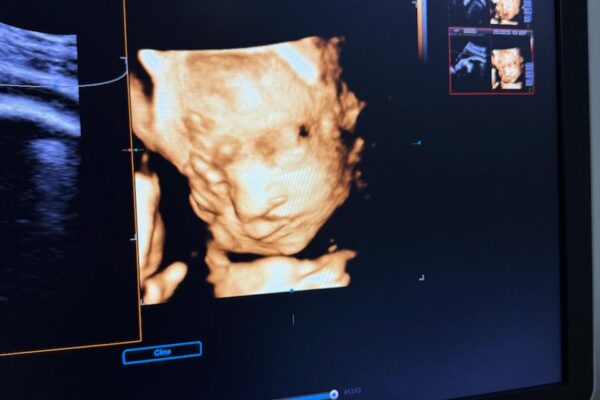

Пеш аз ҳомиладорӣ, дар саршавӣ ё дар давраи пайгирӣ — саволҳо дар бораи доруҳо, бемориҳо, парҳез ва назорати кӯдак одӣ мебошанд. Мо пайгирии мунтазам, ултрасадо ва машваратҳои эҳтиёткорона пешниҳод мекунем.

Маълумот пеш аз ҳомиладорӣ Пайгирии ҳомиладорӣ Ҳомиладории якчандгона